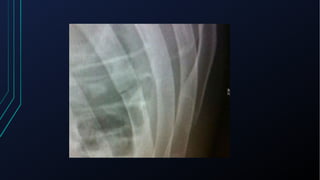

Musculoesqueléticas

• Geralmente pioram com a compressão local ou com o movimento dos

MMSS e tronco

• Costocondrite (Síndrome de Tietze)

• Dor persistente, localizada na região esternal + sinais inflamatórios

• Fratura de costela

• Dor acentuada, localizada na região correspondente

• Piora com a palpação local e respiração

• Herpes Zóster

• Dor contínua, de forte intensidade

• Confirmada com o aparecimento das lesões